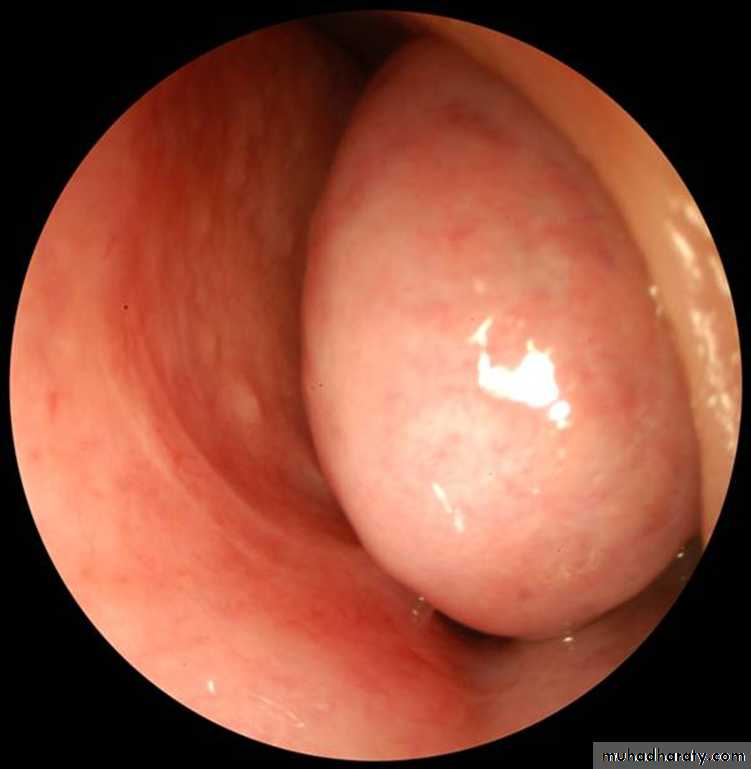

The lateral wall

has three projections of bone called (turbinates or conchae) superior, middle, and inferior nasal conchaeThe space below each concha is called a meatus.

Middle Meatus

The middle turbinate has by far the greatest functional importance.Most of the drainage tracts from the surrounding paranasal sinuses open into the middle meatus.

Maxillary , frontal & anterior ethmoid sinuses

Collectively called anterior group